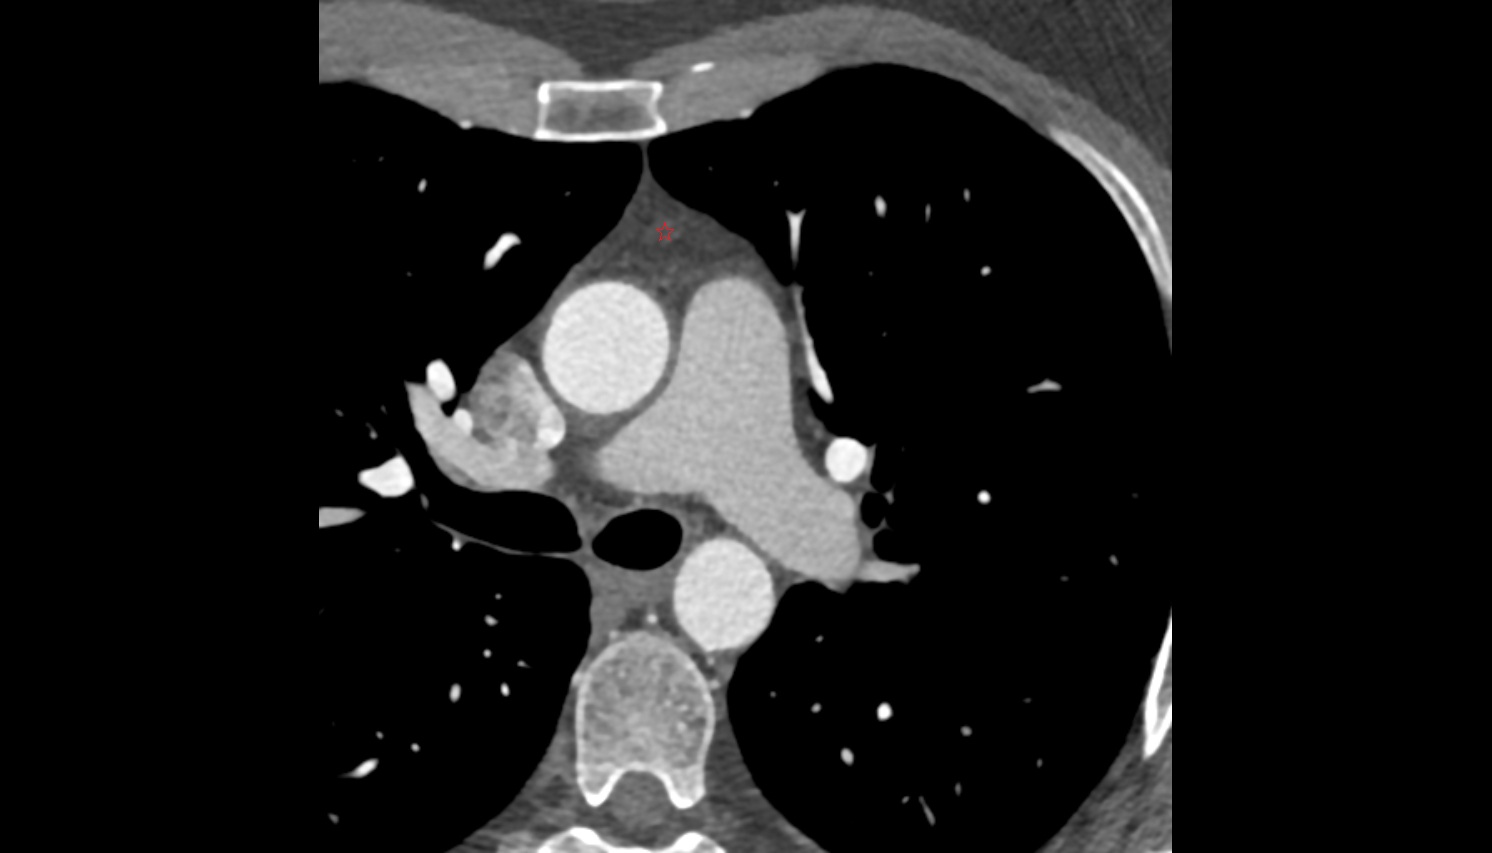

- Heart

- Left ventricle

- Right atrium

- Left atrium

- Right ventricle

- Pulmonary trunk

- Ascending aorta

- Arch of aorta